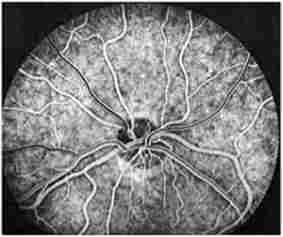

Судини очного дна

Мал. 534. Судини очного дна